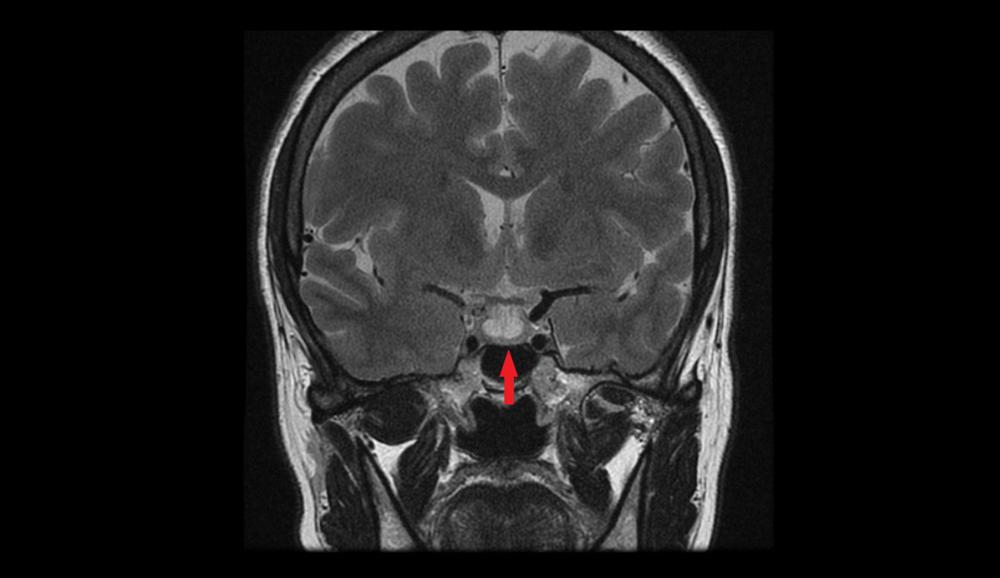

- Pencitraan otak, seperti MRI atau CT scan kepala, untuk mendeteksi tumor pituitari.